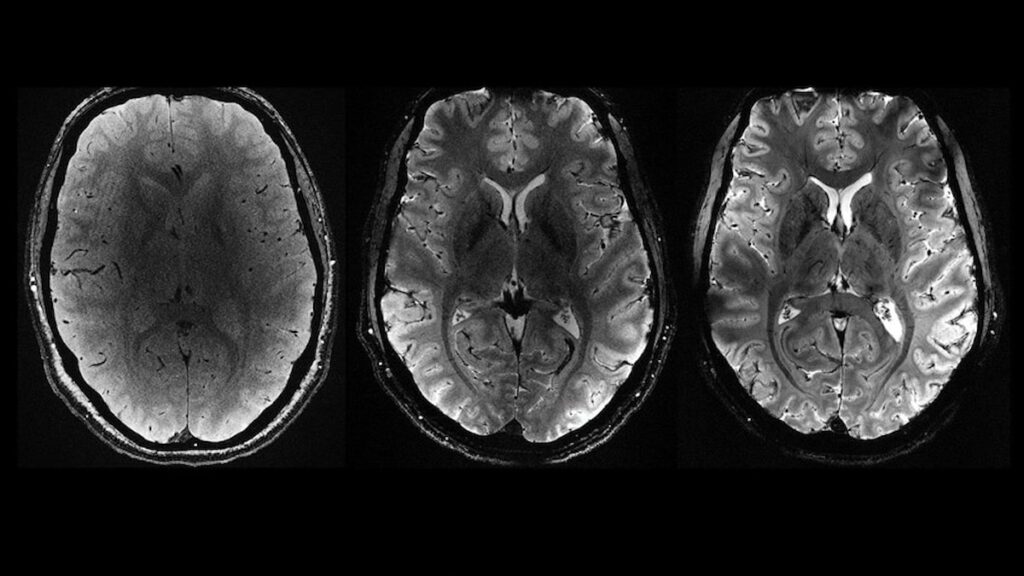

Fransa Atom Enerjisi ve Alternatif Enerjiler Kurumu’ndan (CEA), yapılan yazılı açıklamada “Iseult” adlı MRI cihazıyla çekilen beyin görüntüsünün 20 yıldan uzun süren bir çalışma sonucu elde edildiği belirtildi.

Yapılan çalışmalar kapsamında MRI cihazının son birkaç ay içerisinde yaklaşık 20 sağlıklı gönüllü üzerinde test edildiği kaydedilen açıklamada, neredeyse 4 dakikada en net beyin görüntüsünün elde edildiği aktarıldı.

Açıklamada, 11,7 Tesla manyetik güce sahip Iseult MRI makinesiyle kısa sürede çekilen görüntülerin, hastanelerde yaygın kullanılan cihazlarla elde edilmesinin saatler sürebileceği kaydedildi.